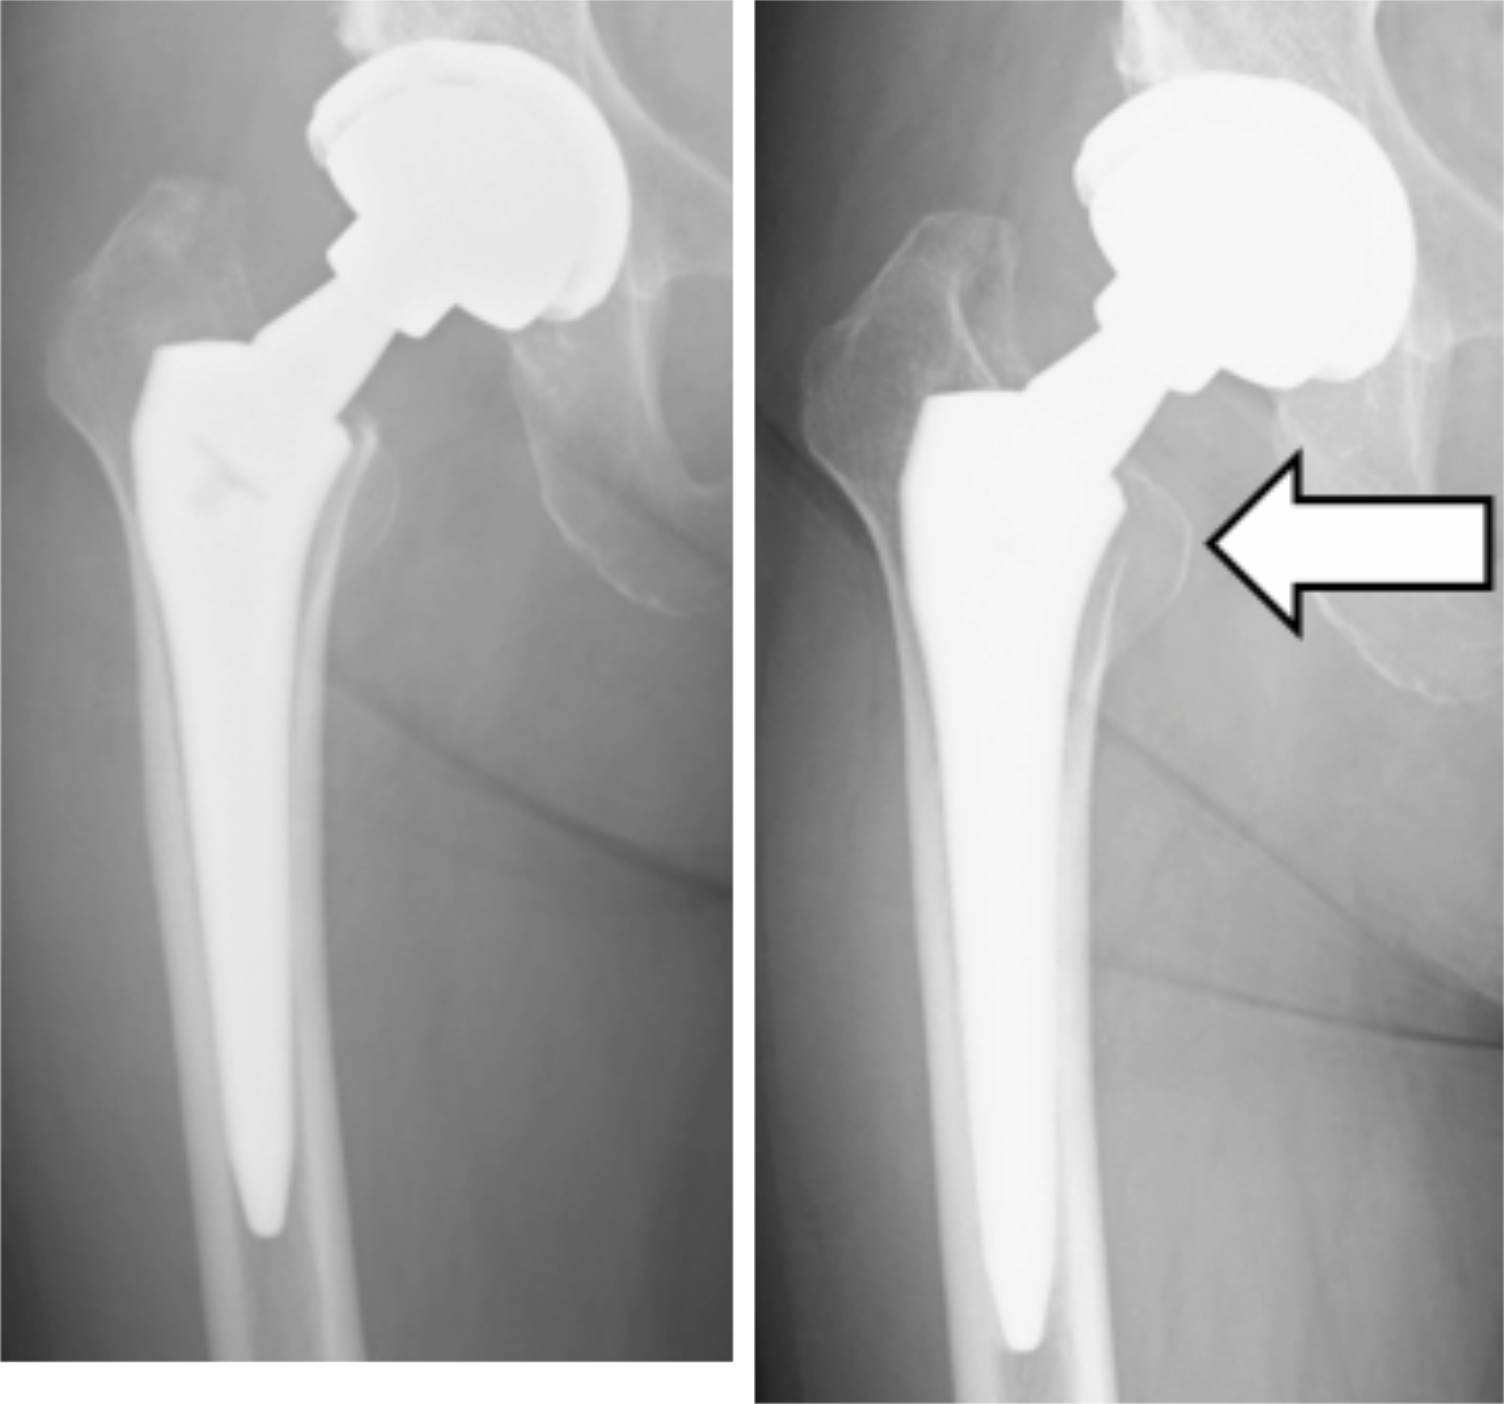

A 69-year-old woman (weight 47 kg, height 144 cm, at initial surgery) underwent a right uncemented THA for osteoarthritis of the hip. The posterolateral surgical approach for THA was. used to implant a 52-mm Trident® acetabular cup with a 3.8-mm thick X3® UHMWXP insert, a Profemur Z® femoral stem with a 4.5° retroverted and 6° varus neck, and a 40-mm Conserve Plus® medium metal head (Figure 6).

Figure 6: Immediate postoperative anteroposterior radiograph of the hip (A), and 3 years after surgery (B) (arrow: osteolysis).

Two months after surgery, she felt discomfort around the right hip joint, but no pain. Although she had a normal range of hip motion, she felt difficulty when she lifted her right leg, and needed a cane to walk. The symptoms continued up to revision surgery. Inflammatory serology was normal. Plain radiographs did not show any impending implant failure, but calcar osteolysis was visible 3 years after implantation (Figure 6). An ultrasound scan showed fluid collection around the hip joint. MRI demonstrated a large pseudotumor around the hip joint (Figure 7). Diagnosed as ARMD, revision surgery was performed.